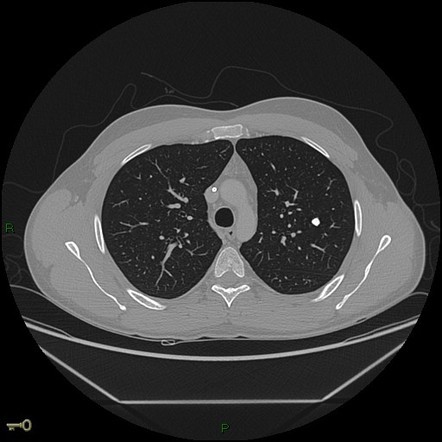

Hallmarks of a granuloma on CT

Smooth margins and central calcification are the hallmarks of residual granulomas. These are very reassuring signs for solitary pulmonary nodules, and usually indicate that cancer is unlikely.